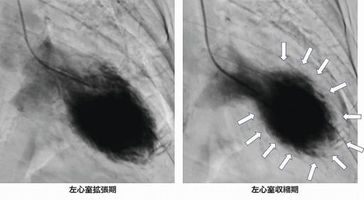

心身健康ドクターに聞く タコつぼ心筋症 循環器内科医 上野勝己さん 2026年1月29日 05:00 タコつぼ心筋症患者の左心室。右の収縮期で、左心室の先端がボール状に膨らんで収縮しないためタコつぼのように見える 松波総合病院心臓疾患センター長(羽島郡笠松町田代) ◆強いストレス発症の引き金 一人... 残り1063文字(全文:1077文字) この記事をお読みいただくには「デジタルプラン」または「宅配+デジタルプラン」の会員登録が必要です。無料会員の方はログインしてマイページからコース変更してください。デジタルプランまたは宅配+デジタルプランをご登録中の方はログインしてください。 岐阜新聞デジタル会員に登録すると 無料会員向け記事が読める ニュースレターで最新情報が受け取れる デジタルプラン、宅配+デジタルプランなら Webオリジナルコンテンツが読める 紙面ビューアが読める チケットの先行発売に参加できる お得なクーポンが使える 新規登録ページ ログインページ トップ 岐阜のニュース 心身健康ドクターに聞く タコつぼ心筋症 循環器内科医 上野勝己さん 関連記事 創作そば隔月ペースで開発 定番は「天麩羅と二八蕎麦」【記者オススメ! ギフテン】 期日前投票、衆院選に市長選に市議補選に…一度にできる? 入場券届かず/国民審査はまだ…有権者混乱 ◇バスケットボール りそなBリーグ1部 ◇水泳 2026ミナモオープンマスターズ競技大会 建て替えの秩父宮ラグビー場 三井住友FGが命名権 バスケットボール きょうBリーグ初のドラフト おすすめ記事 岐阜の野球独立リーグ球団、トライアウトやチームの展望発表 準備室が記者会見 岐阜2区、保守王国の象徴? 過去7回の衆院選データを読み解く 候補者の政党名を間違えて掲示 瑞浪市の期日前投票所、衆院選小選挙区 橋の欄干に車衝突、助手席の妻死亡 中津川の市道、運転の男性も搬送